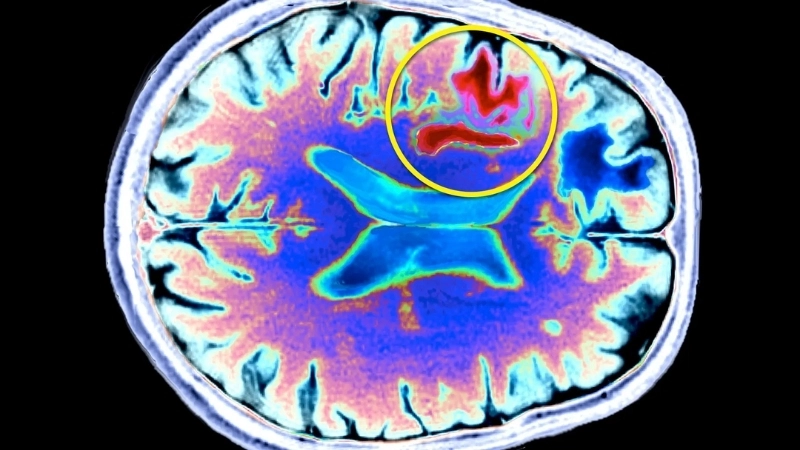

PML diagnosis relies on MRI and JC virus detection